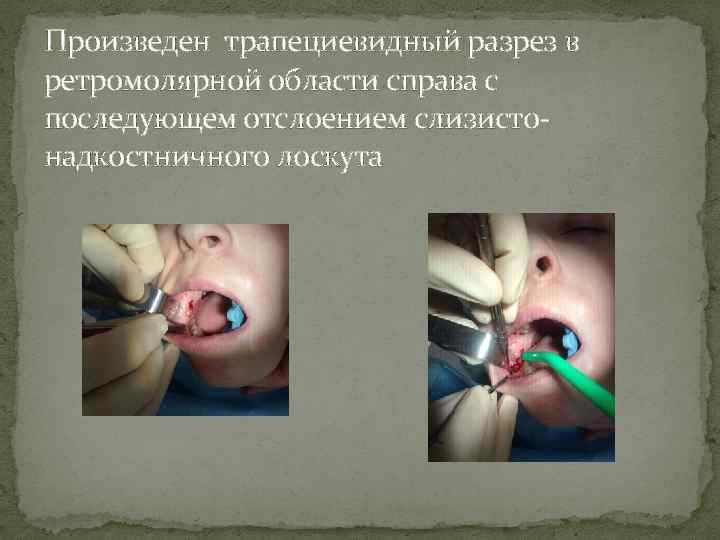

Произведен трапециевидный разрез в ретромолярной области справа с последующем отслоением слизистонадкостничного лоскута

Произведен трапециевидный разрез в ретромолярной области справа с последующем отслоением слизистонадкостничного лоскута